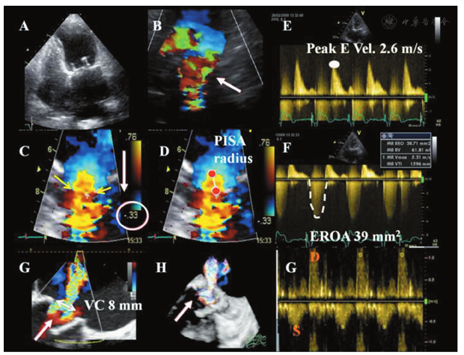

总的来说,以往发表的自体瓣膜反流定量评价的原则和方法可用于PHV反流的评价,但更具有挑战性(图11,图12,图13,图14,图15)[20,21]。事实上,关于这些参数(比如缩流束宽度、EROA、反流量(R Vol))评价PHV的实用性和可靠性的资料有限。而且,通常为偏心性分布的反流束、存在多个射流束、以及人工瓣膜组织产生的阴影效应等原因,使得瓣膜反流的探测与评价更加困难,或受到更多限制。多个多普勒参数可间接提示存在明显的反流(比如在超声声影下的LA顶部存在湍流束)。跨瓣射流束应与瓣周性反流进行鉴别(图16)。目前,推荐结合多种定性、半定量及定量的方法来综合评价PHV反流[14]。

应用彩色多普勒血流可从多个切面观察舒张期流入LV的主动脉瓣反流束。早期研究对AR严重程度的界定多集中在对彩色血流束的特征性描述方面[14,20]。由于血流动力学状态、仪器设置、接受反流的心腔特点、偏心性射流、射流束冲击心腔壁的差异以及来自阅图者的差异,利用反流束的面积和长度判断反流严重程度的方法存在明显的局限性[140]。鉴于彩色反流束的面积和长度与人工瓣AR的程度相关性较差,因此不推荐用于人工瓣AR的定量评价[20]。胸骨旁长轴切面测量的反流束直径/LVOT直径,以及胸骨旁短轴切面贴近人工瓣膜下方测量的反流束面积/LVOT面积,可用来评价中央性反流的严重程度(图11)。反流束直径/LVOT直径>65%提示为重度反流[141]。然而,该方法在偏心性或新月形反流的情况下可能高估反流的严重程度,而在反流束冲击LVOT壁或二尖瓣前叶的情况下可能低估反流严重程度。

对瓣周性AR的半定量评价,需在缝合环水平的短轴切面仔细显示射流束的颈部,以精确定义其周向范围,可用反流束周长占整个缝合环周长的百分比表示反流的严重程度(<10%为轻度,10%~29%为中度,≥30%为重度)(图16)[14,125,142]。然而,这一方法受偏心性反流方向和反流束形状不规则的限制。人工瓣膜的摇摆运动常常提示瓣环开裂>40%,并造成重度反流[143]。在多个切面上观察瓣周反流起始部的宽度也有助于评价反流程度。

由于人工瓣环或支架造成的强回声声影,缩流束宽度(反流束穿过主动脉瓣口的宽度或有效反流面积)在长轴切面上难以正确测量,而在存在多个反流束、反流口形状不规则或瓣周反流的径向扩展等情况下,其测量是不准确的[64]。测量缩流束宽度有助于区分轻度和重度的人工瓣AR。采用Nyquist极限50~60 cm/s时,缩流束宽度<3 mm为轻度AR,而缩流束宽度>6 mm则提示为重度AR。

通常在机械性人工主动脉瓣中难以采用基于近端等速表面积法(PISA)进行定量评价[144,145]。当在存在中央性反流的人工生物瓣膜中采用PISA法时,常常在心尖三腔心或五腔心切面或胸骨旁长轴切面获取血流汇聚带的图像。PISA的半径在舒张期第一血流混叠层进行测量[20]。采用标准公式计算R Vol和EROA。EROA ≥ 30 mm2 或R Vol≥ 60 ml表明重度人工瓣AR。

PISA法评价人工瓣MR是可行的,尤其是在人工生物瓣膜中(图13)。虽然在与反流束方向平行的其他切面上亦可获得,血流汇聚带的显像通常从心尖四腔心切面获得最佳[156,159]。可通过降低显像深度和降低Nyquist极限至15~40 cm/s来优化感兴趣区域。PISA半径在收缩中期首次色彩混叠处测得。R Vol和EROA可由标准公式计算。从定性的角度,Nyquist极限为50~60 cm/s时出现血流汇聚提示存在重度MR。MR严重程度分级将反流分为轻度、中度和重度,又将中度反流细分为"轻-中度"(EROA 20~29 mm2或R Vol 30~44 ml)和"中-重度"(EROA 30~39 mm2或R Vol 45~59 ml)。从定量的角度,如果EROA≥40 mm2且R Vol≥60 ml则人工瓣MR为重度。PISA法具有某些优势和限制性,已在文中阐述。简言之,PISA法是基于在圆形反流口近端速度分布呈半球形对称的假设,这可能不适于偏心性射流束、多股射流束、复杂的或椭圆形的反流口[20]。声影效应也会影响PISA的图像质量。